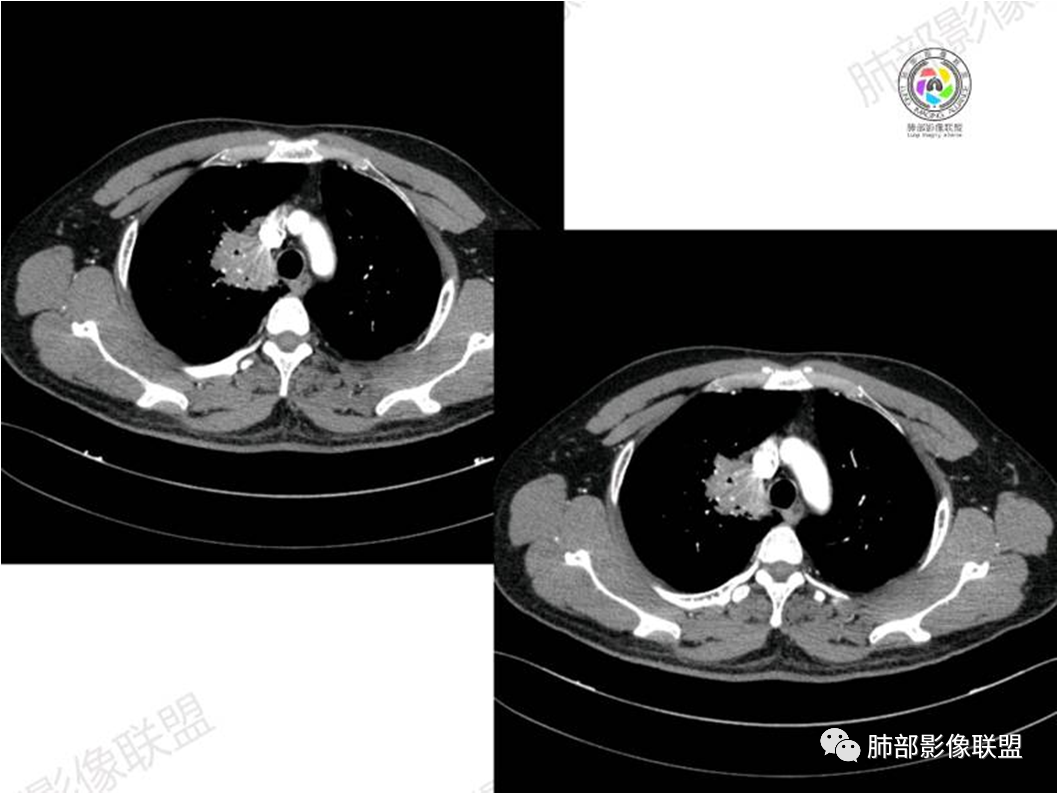

胸部CT:

中年男性,偶有咳嗽,右肺上叶近纵膈旁占位,内可见僵硬的支气管和小空泡征,病灶边缘可见分叶,毛刺,增强病灶中度以上不均匀强化,可见血管造影征,考虑恶性病变,腺癌可能性大。

右肺上叶纵隔胸膜侧一实性肿块,与纵隔胸膜宽基底相连,局部脂肪间隙消失,形态欠规则,内部可见多个小空泡,平扫密度尚均匀,增强后可见点条状强化,内部穿行血管,周围肺组织干净,纵隔淋巴结略肿大,男性44岁,只有咳嗽,考虑恶性肿瘤,腺癌,鳞癌。鉴别结核,OP,炎性假瘤。

右肺上叶近纵膈旁肿块,密度均匀,边缘分叶,毛刺,气管受压变窄,不均匀强化,可见血管造影征,考虑淋巴瘤,鉴别炎性假瘤。

中年男性,右肺上叶纵隔旁软组织肿块,边缘膨隆、毛糙,可见多发分叶,支气管穿行,部分截断,增强后密度欠均匀,纵隔内见多发小淋巴结,首先考虑恶性,腺癌,鉴别淋巴瘤

中年男性,右肺上叶纵隔旁肿瘤,稍膨隆,有毛刺,支气管穿行,远端闭塞,强化均匀,血管走行尚可,考虑淋巴瘤可能性大(支气管远端闭塞,不太符合),鉴别腺癌(气管穿行后闭塞,不太符合),op(病灶稍膨隆)

患者中年男性,咳嗽就诊,无其他不适。胸部CT:右肺上叶尖段上纵膈旁肿块,边界清楚,边缘光滑,内见支气管受压变窄,伴阻塞性改变,增强均匀强化,见血管造影征。综合考虑恶性病变,小细胞肺癌或淋巴瘤。气管镜活检应能明确。

中年男性,右肺上叶纵隔旁实性病灶,边缘有彭隆,有平直,有分叶,有尖角,病灶边缘中心可见支气管征,周围少许磨玻璃,边缘模糊,增强后动脉期病灶可见强化血管影,渐进性强化,临近血管界限清晰。考虑炎性病灶,普通炎性肉芽肿?结核?炎性肌纤维母细胞瘤?鉴别腺癌,淋巴瘤

③扩张的充气支气管为其较特征性的表现,出现率约为89%,支气管管壁无破坏,支气管常扩张并达病灶的边缘,这与炎症性肺癌明显不同,其病理学基础是肿瘤起源于肺间质,肿瘤细胞沿着脏器解剖结构生长,周围增生的结缔组织牵拉导致支气管扩张,因而这类支气管扩张在肿瘤治疗后有时可消失;

④血管造影征是另一 点,强化的肺血管形态及走行正常,无扭曲或增 粗,其病理学基础为肿瘤细胞沿间质增生浸润,不破坏血管或支气管,病灶内肺支架结构完整,本研究发现率为75%;

⑤病灶多为中度强化,部分轻度强化;